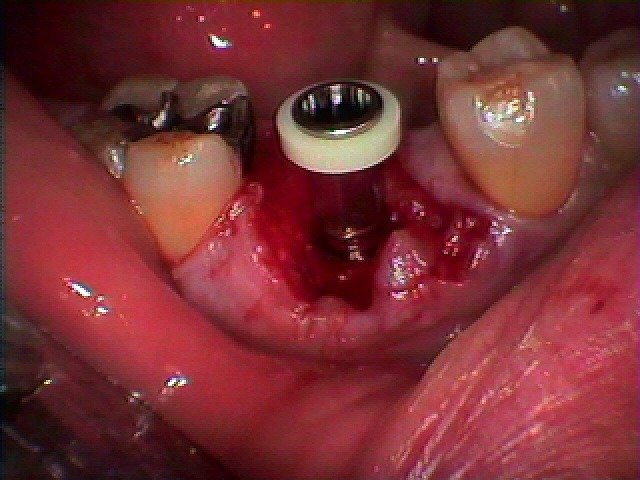

インプラント埋入時になります

骨補填材を転入しています

インプラント埋入時になります

5mmの11,5mmというインプラントを埋入しています

綺麗に入りました